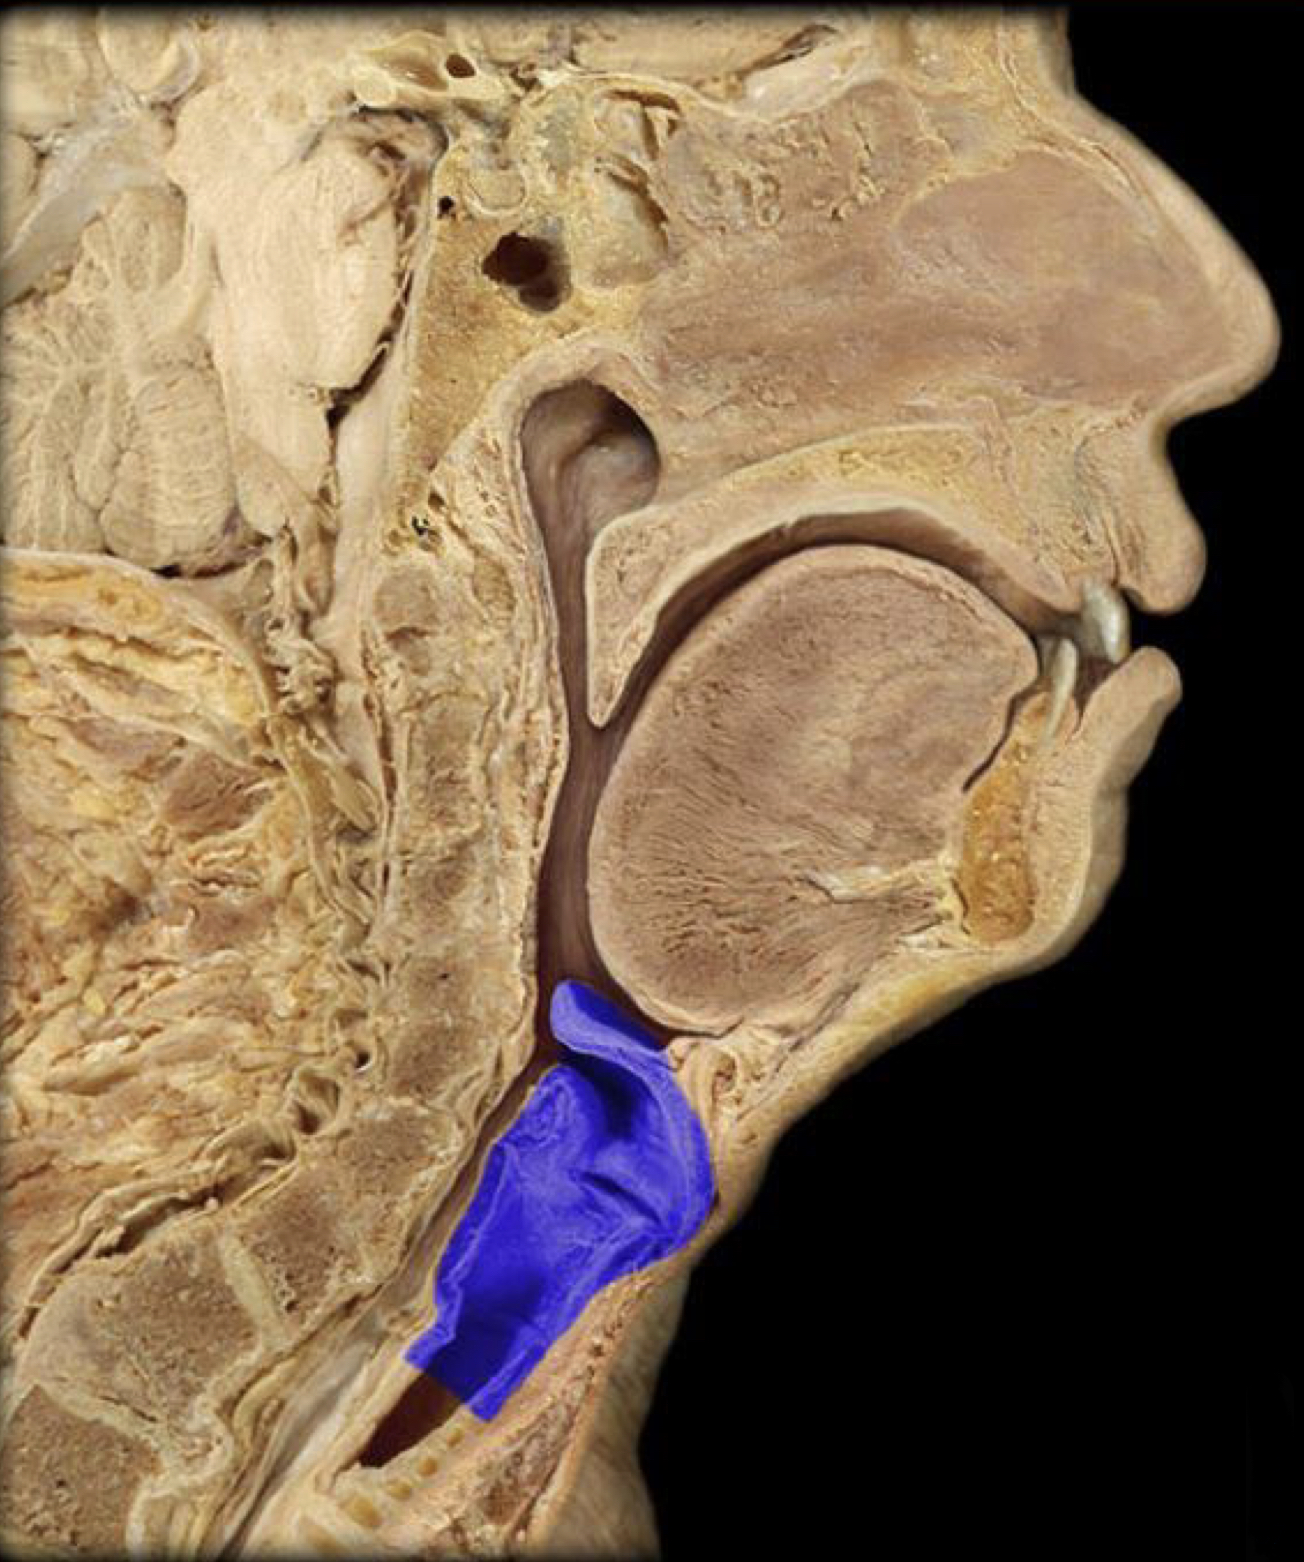

What structure is highlighted in blue?

Laryngooharynx